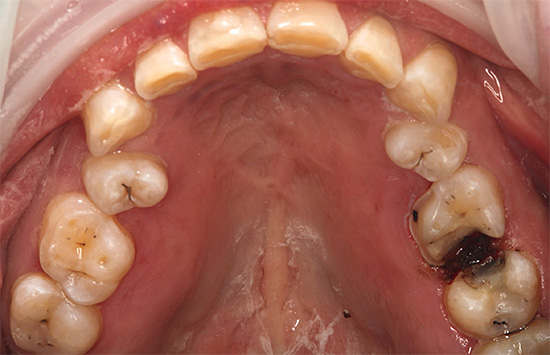

- Não há pontos e traços pretos (os últimos são característicos de cárie de fissura).

Se houver um orifício no esmalte (cavidade), definitivamente não será possível curar um dente sem obtê-lo. Em muitos casos, essas lesões de cárie que só podem ser tratadas por um dentista se apresentam como manchas marrons ou pretas distintas.

Isso é especialmente verdadeiro para fissuras, onde esses pontos às vezes podem ser muito pequenos e não se incomodam com nada, e é por isso que muitos não os percebem como um problema sério. Enquanto isso, a área da lesão sob essa mancha já pode penetrar profundamente na dentina.

Devido ao pequeno tamanho das áreas escuras na área da fissura, muitos acreditam que esses pontos podem simplesmente ser clareados ou lixados em casa, e a cárie dentária como se isso fosse curado. De fato, essa mancha é apenas um sinal de que a cárie não pode ser curada sem preenchimento.